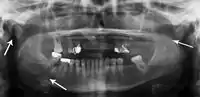

Panoramic radiograph of a simple mandible fracture of the right mandibular body, minimally displaced. Note that the teeth to the left of the fracture do not touch

Panoramic radiographs are tomograms where the mandible is in the focal trough and show a flat image of the mandible. Because the curve of the mandible appears in a 2-dimensional image, fractures are easier to spot leading to an accuracy similar to CT except in the condyle region. In addition, broken, missing or malaligned teeth can often be appreciated on a panoramic image which is frequently lost in plain films. Medial/lateral displacement of the fracture segments and especially the condyle are difficult to gauge so the view is sometimes augmented with plain film radiography or computed tomography for more complex mandible fractures.